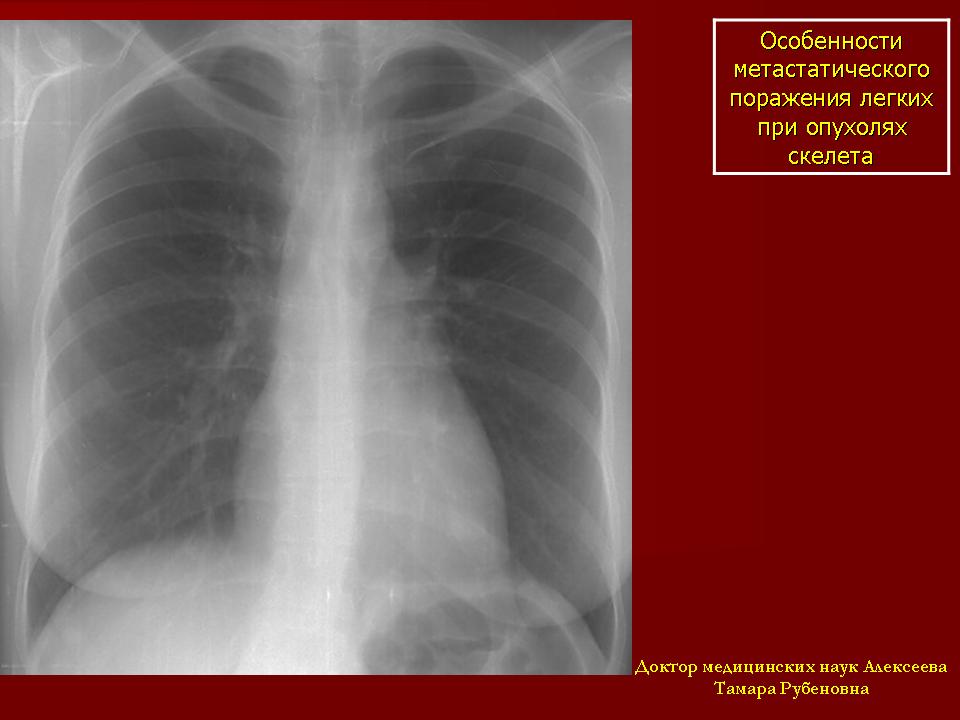

Особенности метастатического поражения легких при опухолях скелета

Остеогенные саркомы наиболее злокачественные быстро прогрессирующие и рано метастазирующие опухоли скелета.

Для опухолей костей характерен гематогенный путь метастазирования, при котором наиболее часто отмечается изолированное поражение легочной ткани в виде солитарных или множественных очагов и фокусов уплотнения небольших размеров от 0,5см до 1,5-2,5см. Учитывая патологоанатомические варианты остеосарком метастазы в легочной ткани по своим скиологическим признакам напоминают строение первичной опухоли, поэтому структура их неоднородна за счет очажков обызвествлений